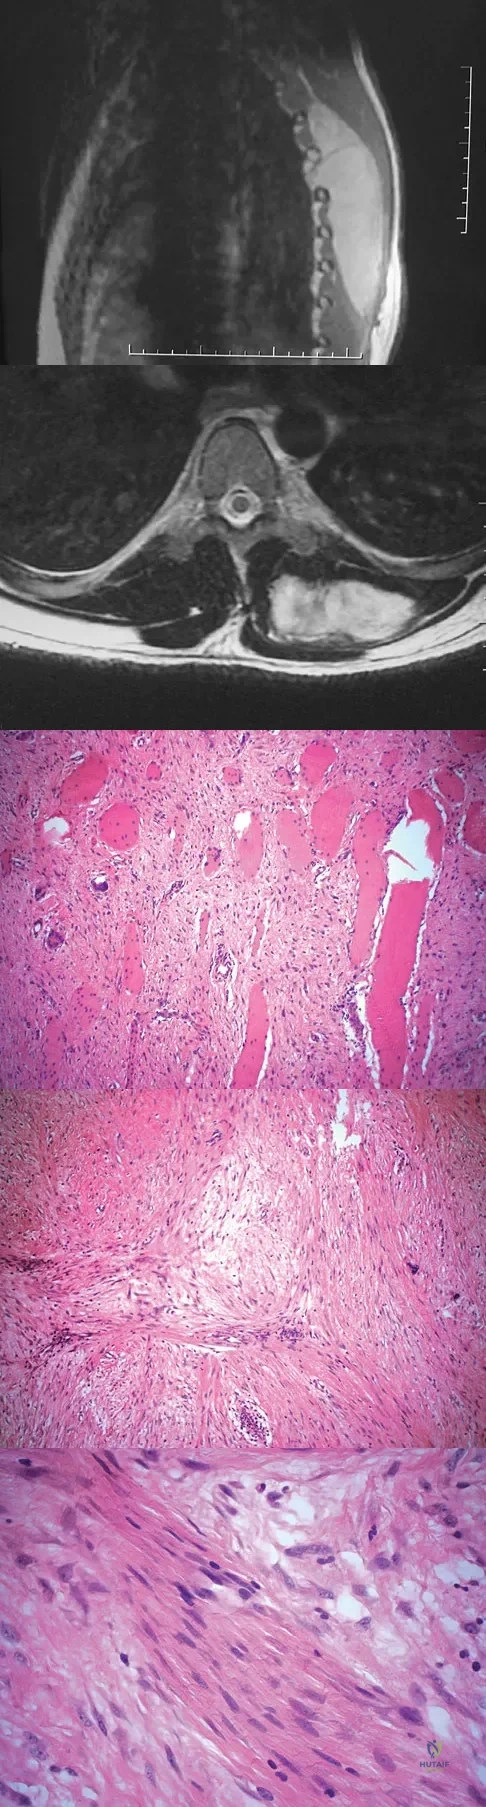

A 38-year-old man has an enlarging left paraspinal soft-tissue mass. Based on the MRI scans and biopsy specimens shown in Figures 32a through 32e, what is the most likely diagnosis?